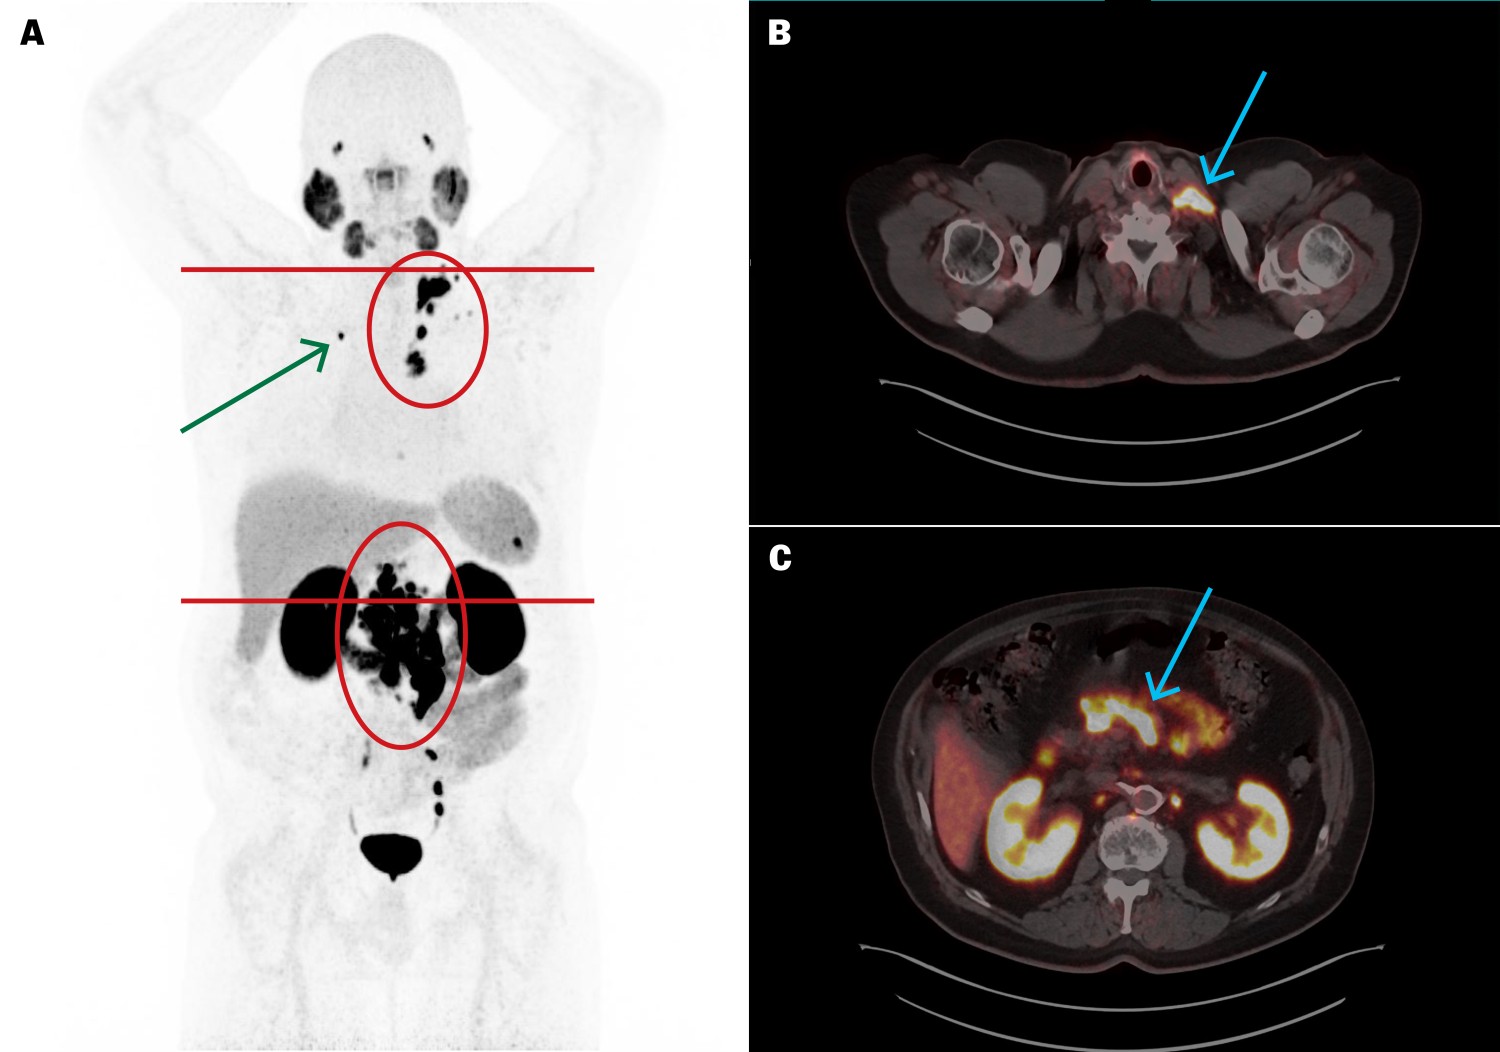

PSA in plasma (p-PSA, reference range 0–4.0 µg/L for men ≥ 60 years) was 154 µg/L and the PSA doubling time was 4.5 months. PET/CT with the Gallium-68-labelled radiopharmaceutical tracer prostate-specific membrane antigen radioligand (PSMA-RL) ([⁶⁸Ga]PSMA-11) revealed high uptake in scattered metastatic lymph nodes in the pelvis, abdomen, chest and neck, as well as a solitary bone metastasis in the right clavicle (Figure 1). The uptake indicated possible suitability for treatment with Lutetium-177 (a beta-emitting radionuclide) PSMA radioligand therapy ([¹⁷⁷Lu]PSMA-RL).